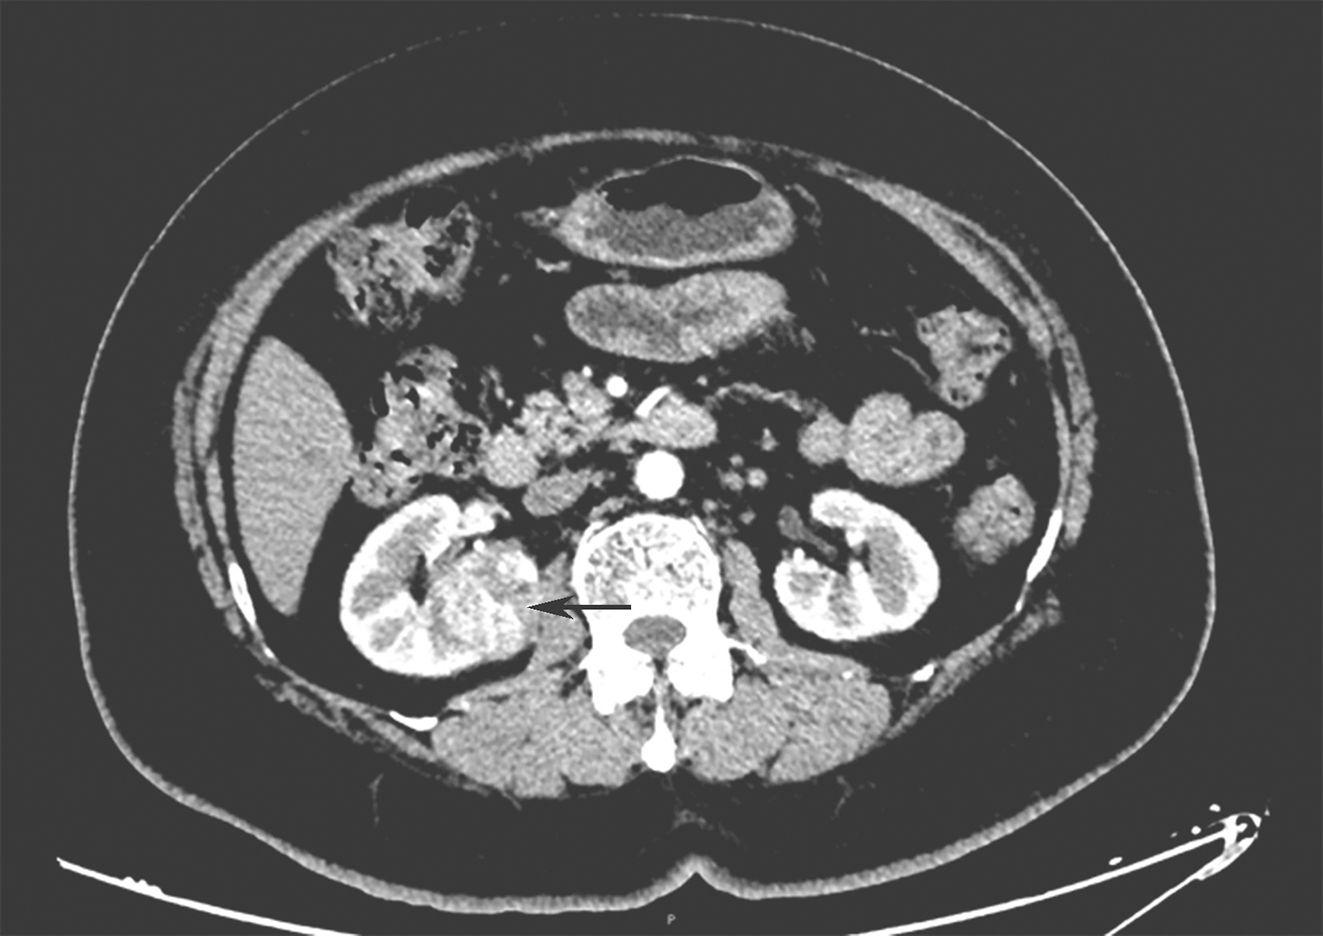

全腹、盆腔平扫加增强CT:①胃窦后上壁见类圆形肿块影:5.7cm×4.0cm×4.6cm,增强扫描渐进性强化,其内见低密度无强化影:胃肠间质瘤可能(图1)。②右肾中部3.4cm×3.7cm肿块影,增强扫描强化不均,延迟期强化程度减低,肾脏恶性肿瘤性病变可能(图2)。胰腺、脾脏、左肾及膀胱未见明显异常密度影,双侧附件区未见明显异常结节影(图 3)。

图2腹部增强CT示右肾中部肿块(横断位)

图3腹部增强CT同时显示两处肿瘤